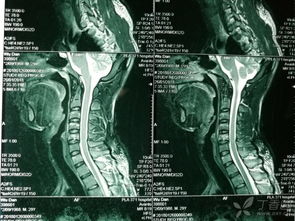

因?yàn)轭i骨骨折也就是頸部脊椎骨的骨 折,在脊椎骨中央有神經(jīng)通過,這些神經(jīng)像電纜一樣能把大腦的命令傳達(dá)到全身,又能把身體的感覺傳向大腦。如果骨折切斷或壓迫脊椎骨中的神經(jīng),頸以下就會(huì)完 全麻痹,有時(shí)會(huì)使呼吸停止。

3、頸椎骨折常見于跳水誤跳入淺游泳池,或從很高的地方墜落以及交通事故等。

體位護(hù)理和體溫監(jiān)測(cè) 保持頭、頸、肩一致性活動(dòng),防止頸椎錯(cuò)位。翻身時(shí)要一個(gè)人固定頭部,一個(gè)人搬動(dòng)軀干,并注意顱骨牽引,防止滑脫,保持牽引繩與軀干在同一軸線上,床頭抬高15°~30°。顱骨牽引鋼針口處滴75%酒精4~5滴,每日更換敷料一次。由于脊髓損傷,植物神經(jīng)功能紊亂,全身交感神經(jīng)支被切斷,不能適應(yīng)周圍環(huán)境溫度的變化而出現(xiàn)高熱,病人一旦出現(xiàn)高熱,體溫>38.5℃(腋下),即給予物理降溫,必要時(shí)給4℃冰生理鹽水300ml低壓灌腸,采取積極措施降溫。